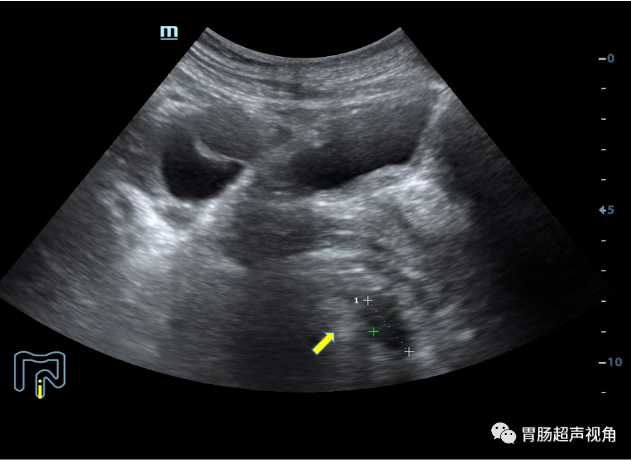

• 直肠灌入300ml造影剂经腹探查:直肠肠腔重度狭窄,仅见液体呈线状迂曲缓慢进入。

• 直肠肠壁可见多发低回声结节向腔内隆起,较大着位于直肠后壁,大小约5.2x3.3x2.0cm(长x宽x厚),前壁另可见片状不规则增厚,较厚处约1.1cm,累及长度约4.0cm(环绕肠壁约1/2周),肠粘膜面可见一较大凹陷,长约2.2cm,深约0.7cm,粘膜凹陷处可见强回声附着。

• 逆行经肛门灌入造影剂,直肠腔明显狭窄,造影剂迂曲缓慢进入直肠腔